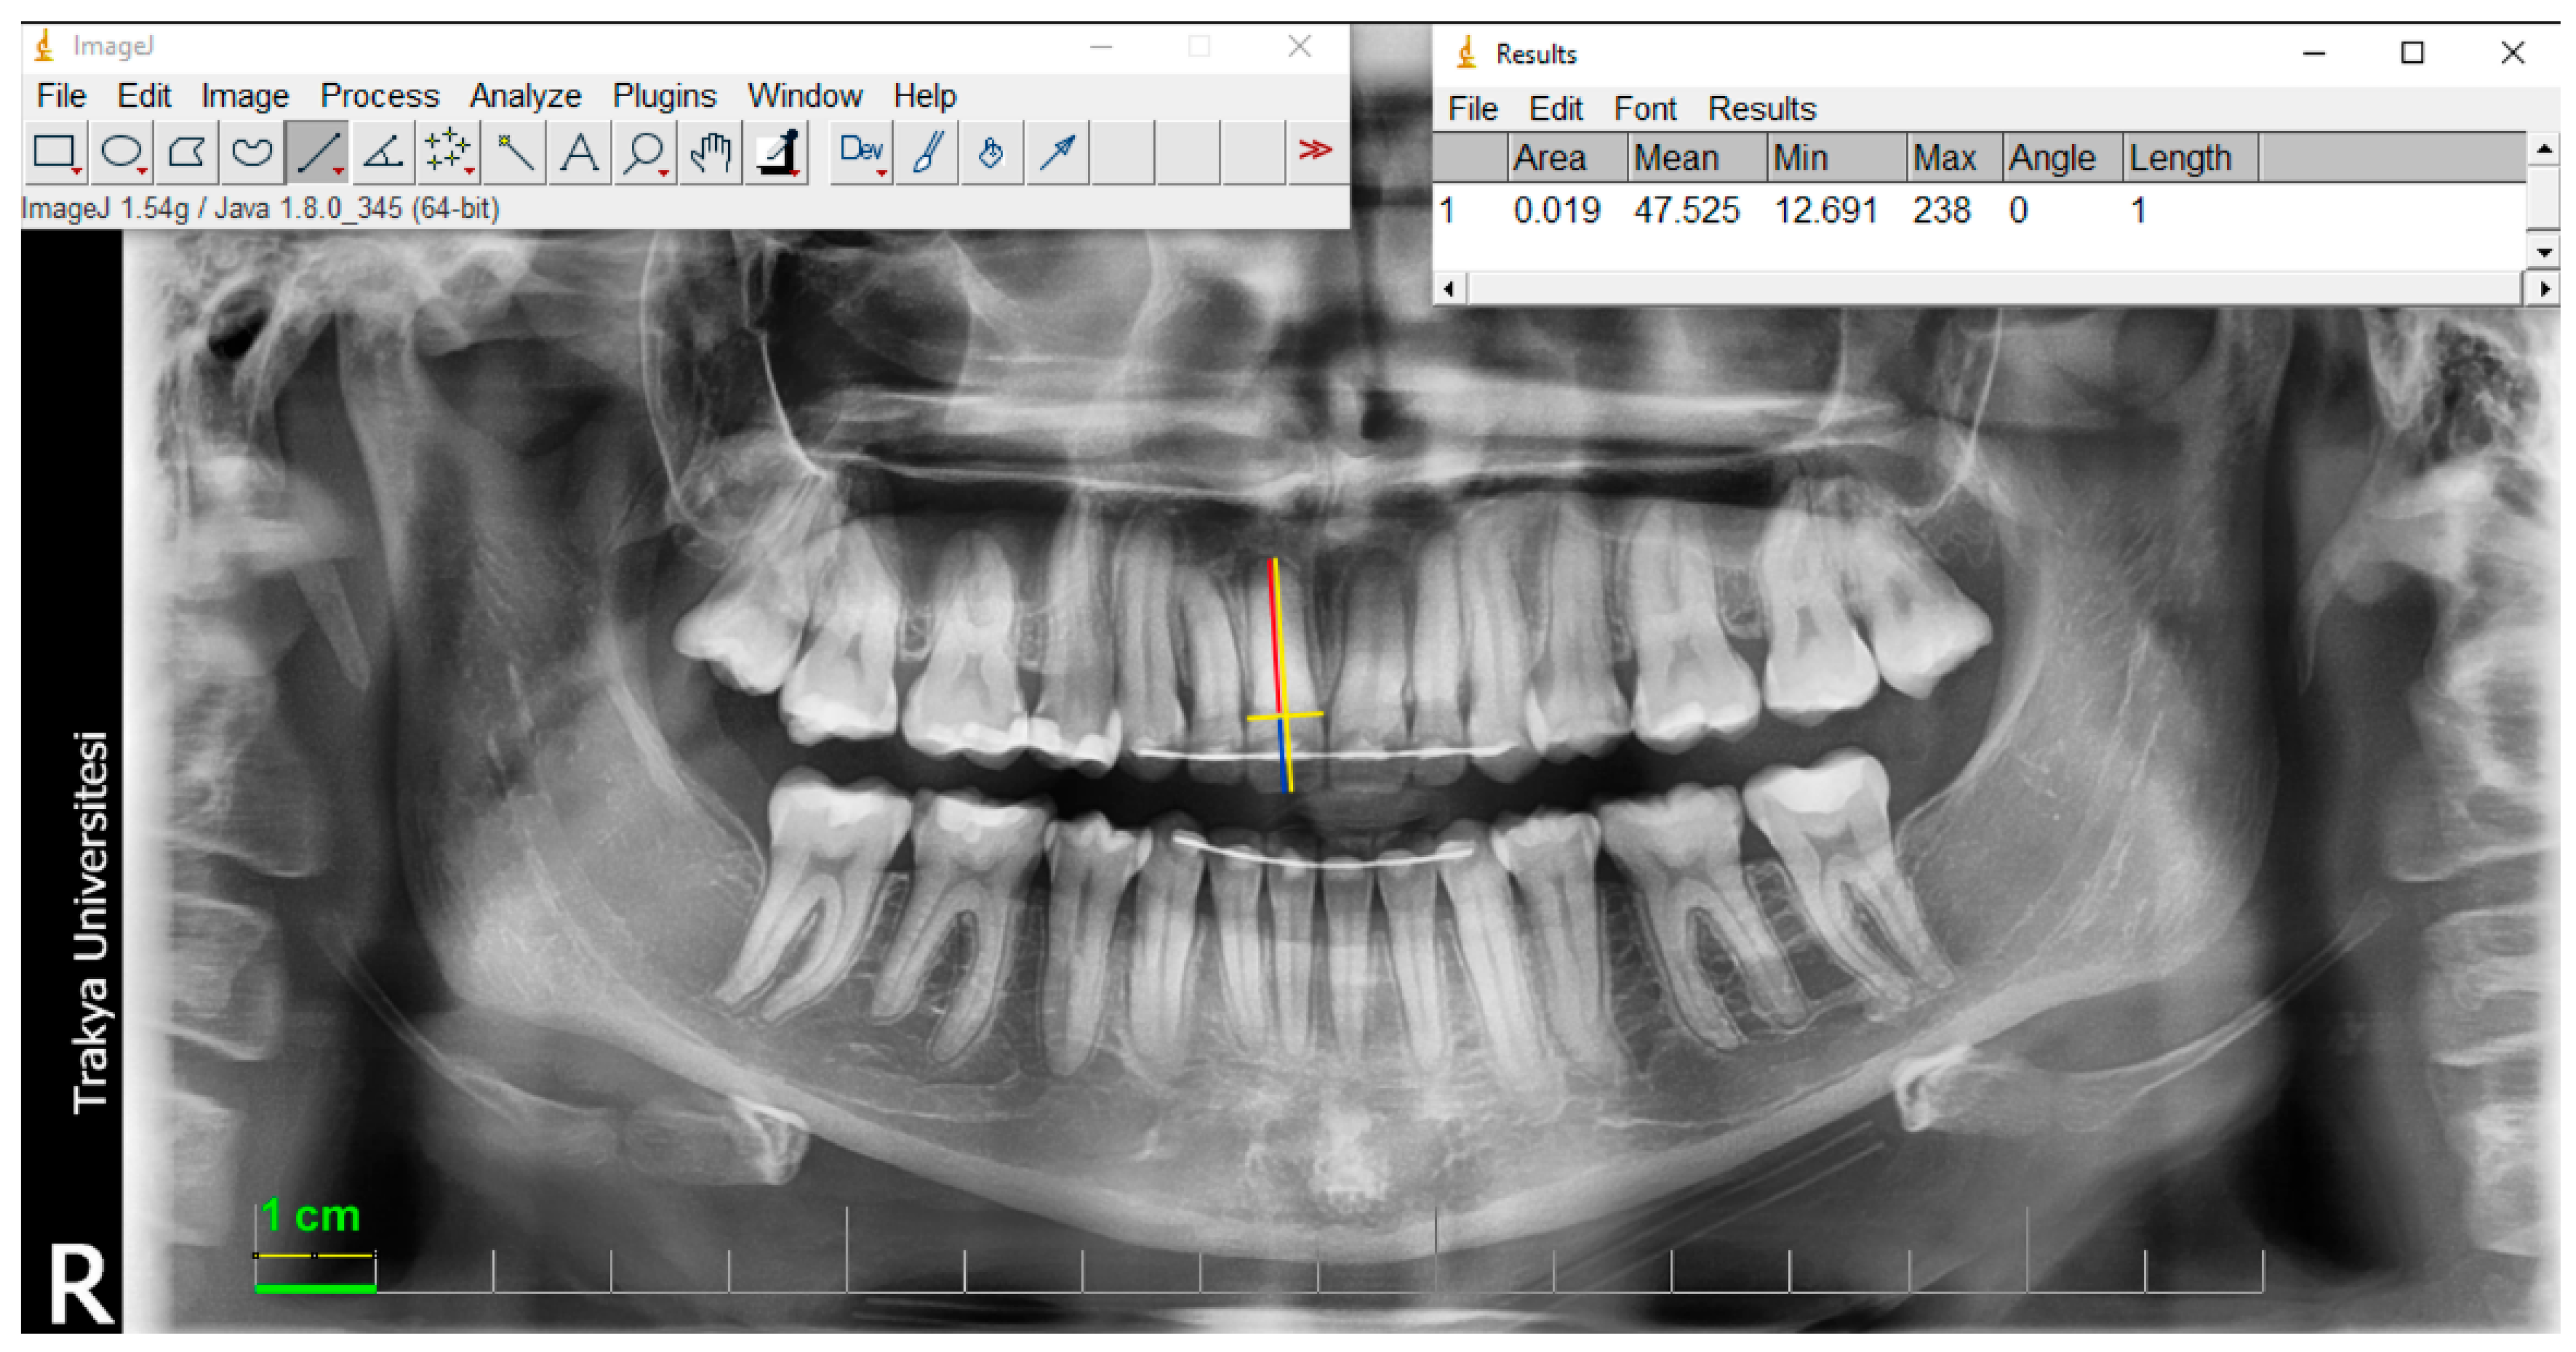

2.2. Radiography and Measurements